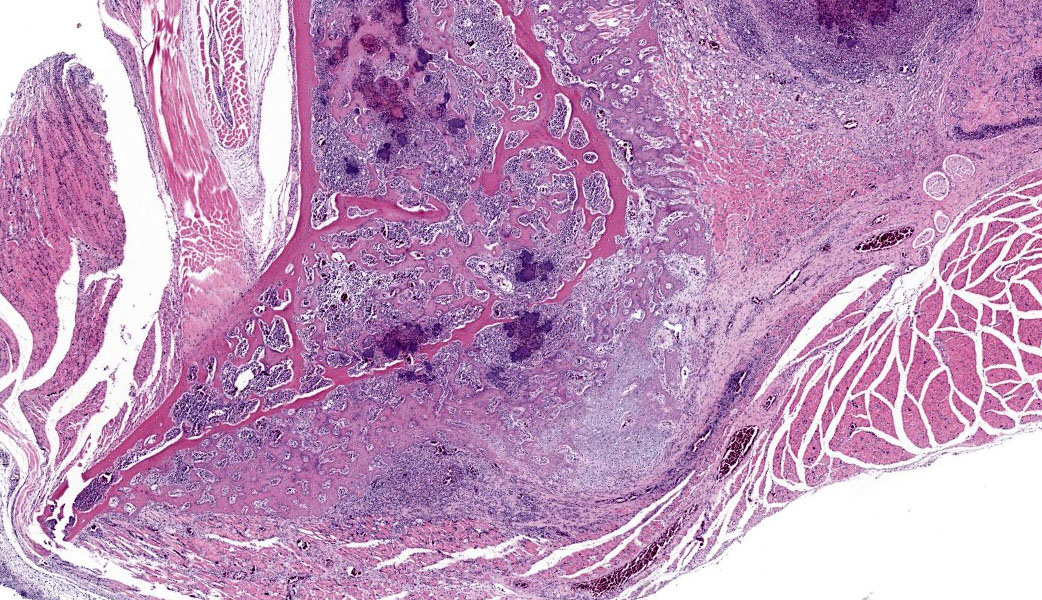

Microscopic Description:

Bones and adjacent soft tissue. Multifocally throughout bone, synovial joint and muscle tissue and affecting approximately 60% of the tissue examined, there are severe, multifocal to coalescing inflammatory infiltrates. The inflammation is chiefly composed of degenerate heterophils, with fewer lymphocytes and plasma cells, embedded in eosinophilic mate-rial showing no cellular outlines (lytic necrosis) with nuclear fragmentation and loss (karyorrhexis and karyolysis); embedded within the necro-inflammatory process are common , up 100 micrometers in diameter, coccobacillary bacterial colonies; in some foci, the necro-inflammatory foci are bordered by macrophages forming multinucleated giant cells containing a 15-50 nuclei with a horse-shoe arrangement with occasional foamy cytoplasm. The inflamed bones show reduction of medullary bony trabeculae (osteolysis), with multifocal scalloping and thinning of the remaining ones with an increased basophilic hue while other show empty lacunae and diffuse eosinophilia (osteonecrosis); the periosteum instead shows a common exophytic proliferation of the cortical bone with cartilage and woven bone formation (periosteal reaction).

The inflammatory infiltrate is also observed infiltrating and filling multifocal synovial joint lumina and capsules (arthrosynovitis), with a layer of fibrin embedding heterophils and covering multifocally the articular carti-age, which shows increase eosinophilia (cartilage degeneration).

The adjacent rhabdomyocytes exhibit multifocal reduction in size and diameter, with angu-lar edges (muscular atrophy) with the closest one to the inflammation exhibiting an amphophilic sarcoplasm and linear arranged central nuclei (myotubes) and rare areas of endomysial fibrosis.

- Bone: multifocal to coalescing, severe, subacute, heterophilic and necrotizing osteomyelitis, with osteolysis, perio-teal reaction, osteonecrosis and with intralesional bacterial colonies.

- Synovial joints: diffuse, severe, sub-acute, fibrinous and heterophilic ar-thro-synovitis with intralesional bacte-rial colonies.

- Skeletal muscle: Severe, multifocal, subacute, heterophilic and necrotizing myositis with intralesional bacterial

- Wing: Osteomyelitis, tenosynovitis, myositis, and cellulitis, necrotizing and heterophilic, chronic, multifocal, severe, with pannus and large colonies of bacteria.

- Skeletal muscle, adipose tissue: Atrophy, chronic, diffuse, severe.

The avian skeletal system has several unique functional adaptations. Birds have three types of bone: pneumatic, hematopoietic, and medullary.5 Pneumatic bones have air sacs in the endosteum in place of bone marrow. The number and distribution of pneumatic bones varies by species, but most birds have pneumatic hu-meri, femurs, sternums, and skulls.5 The remainder of the bones are hematopoietic and have bone marrow. Medullary bone is present in female birds prior to laying eggs when they deposit calcium on the endosteum, with de-posits filling the marrow cavity of long bones.5 Additionally, many bones are fused(e.g., tibiotarsus, synsacrum, etc.). The slide in this case had a pneumatic bone that articulated with two hematopoietic long bones sur-rounded by abundant skeletal muscle; this consistent with wing where the humerus (pneumatic bone) articulates with the radius and ulna (hematopoietic bones). The leg (at the articular of the femur and tibiotarsus) was also considered, but the amount of skeletal muscle was deemed to be excessive for this lo-cation. Foci of inflammation and necrosis were present in both pneumatic and hemato-poietic bone, suggestive of systemic bacterial sepsis.

Many classic features of bone and joint inflammation and healing were demonstrated in this case, including osteonecrosis and periosteal new bone formation (characterized by lattices of woven bone oriented perpendicularly to the bone’s long axis). In addition to the excellent description provided by the contributor, conference participants also noted de-creased basophilia of the articular cartilage. This is a common finding of arthritis and correlates to loss of proteoglycans in the chondroid matrix.2 Additionally, one of the joints was overlain by a thin layer of fibrovascular tissue, consistent with pannus. Pannus is caused by proliferation of stromal cells in chronic arthritis and was nicely highlighted with a Masson’s trichrome stain.2